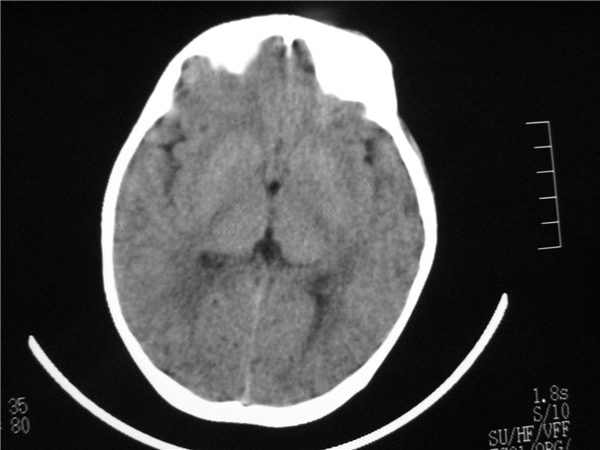

标题: PED2843: CT-23675 F 4Y 大家看看颅内有问题没。 [打印本页]

标题: PED2843: CT-23675 F 4Y 大家看看颅内有问题没。

四脑室扩大,三脑室稍扩大上移

六脑室

四脑室扩大,,六脑室

四脑室扩大,密度降低,图像的问题?建议mr扫描。